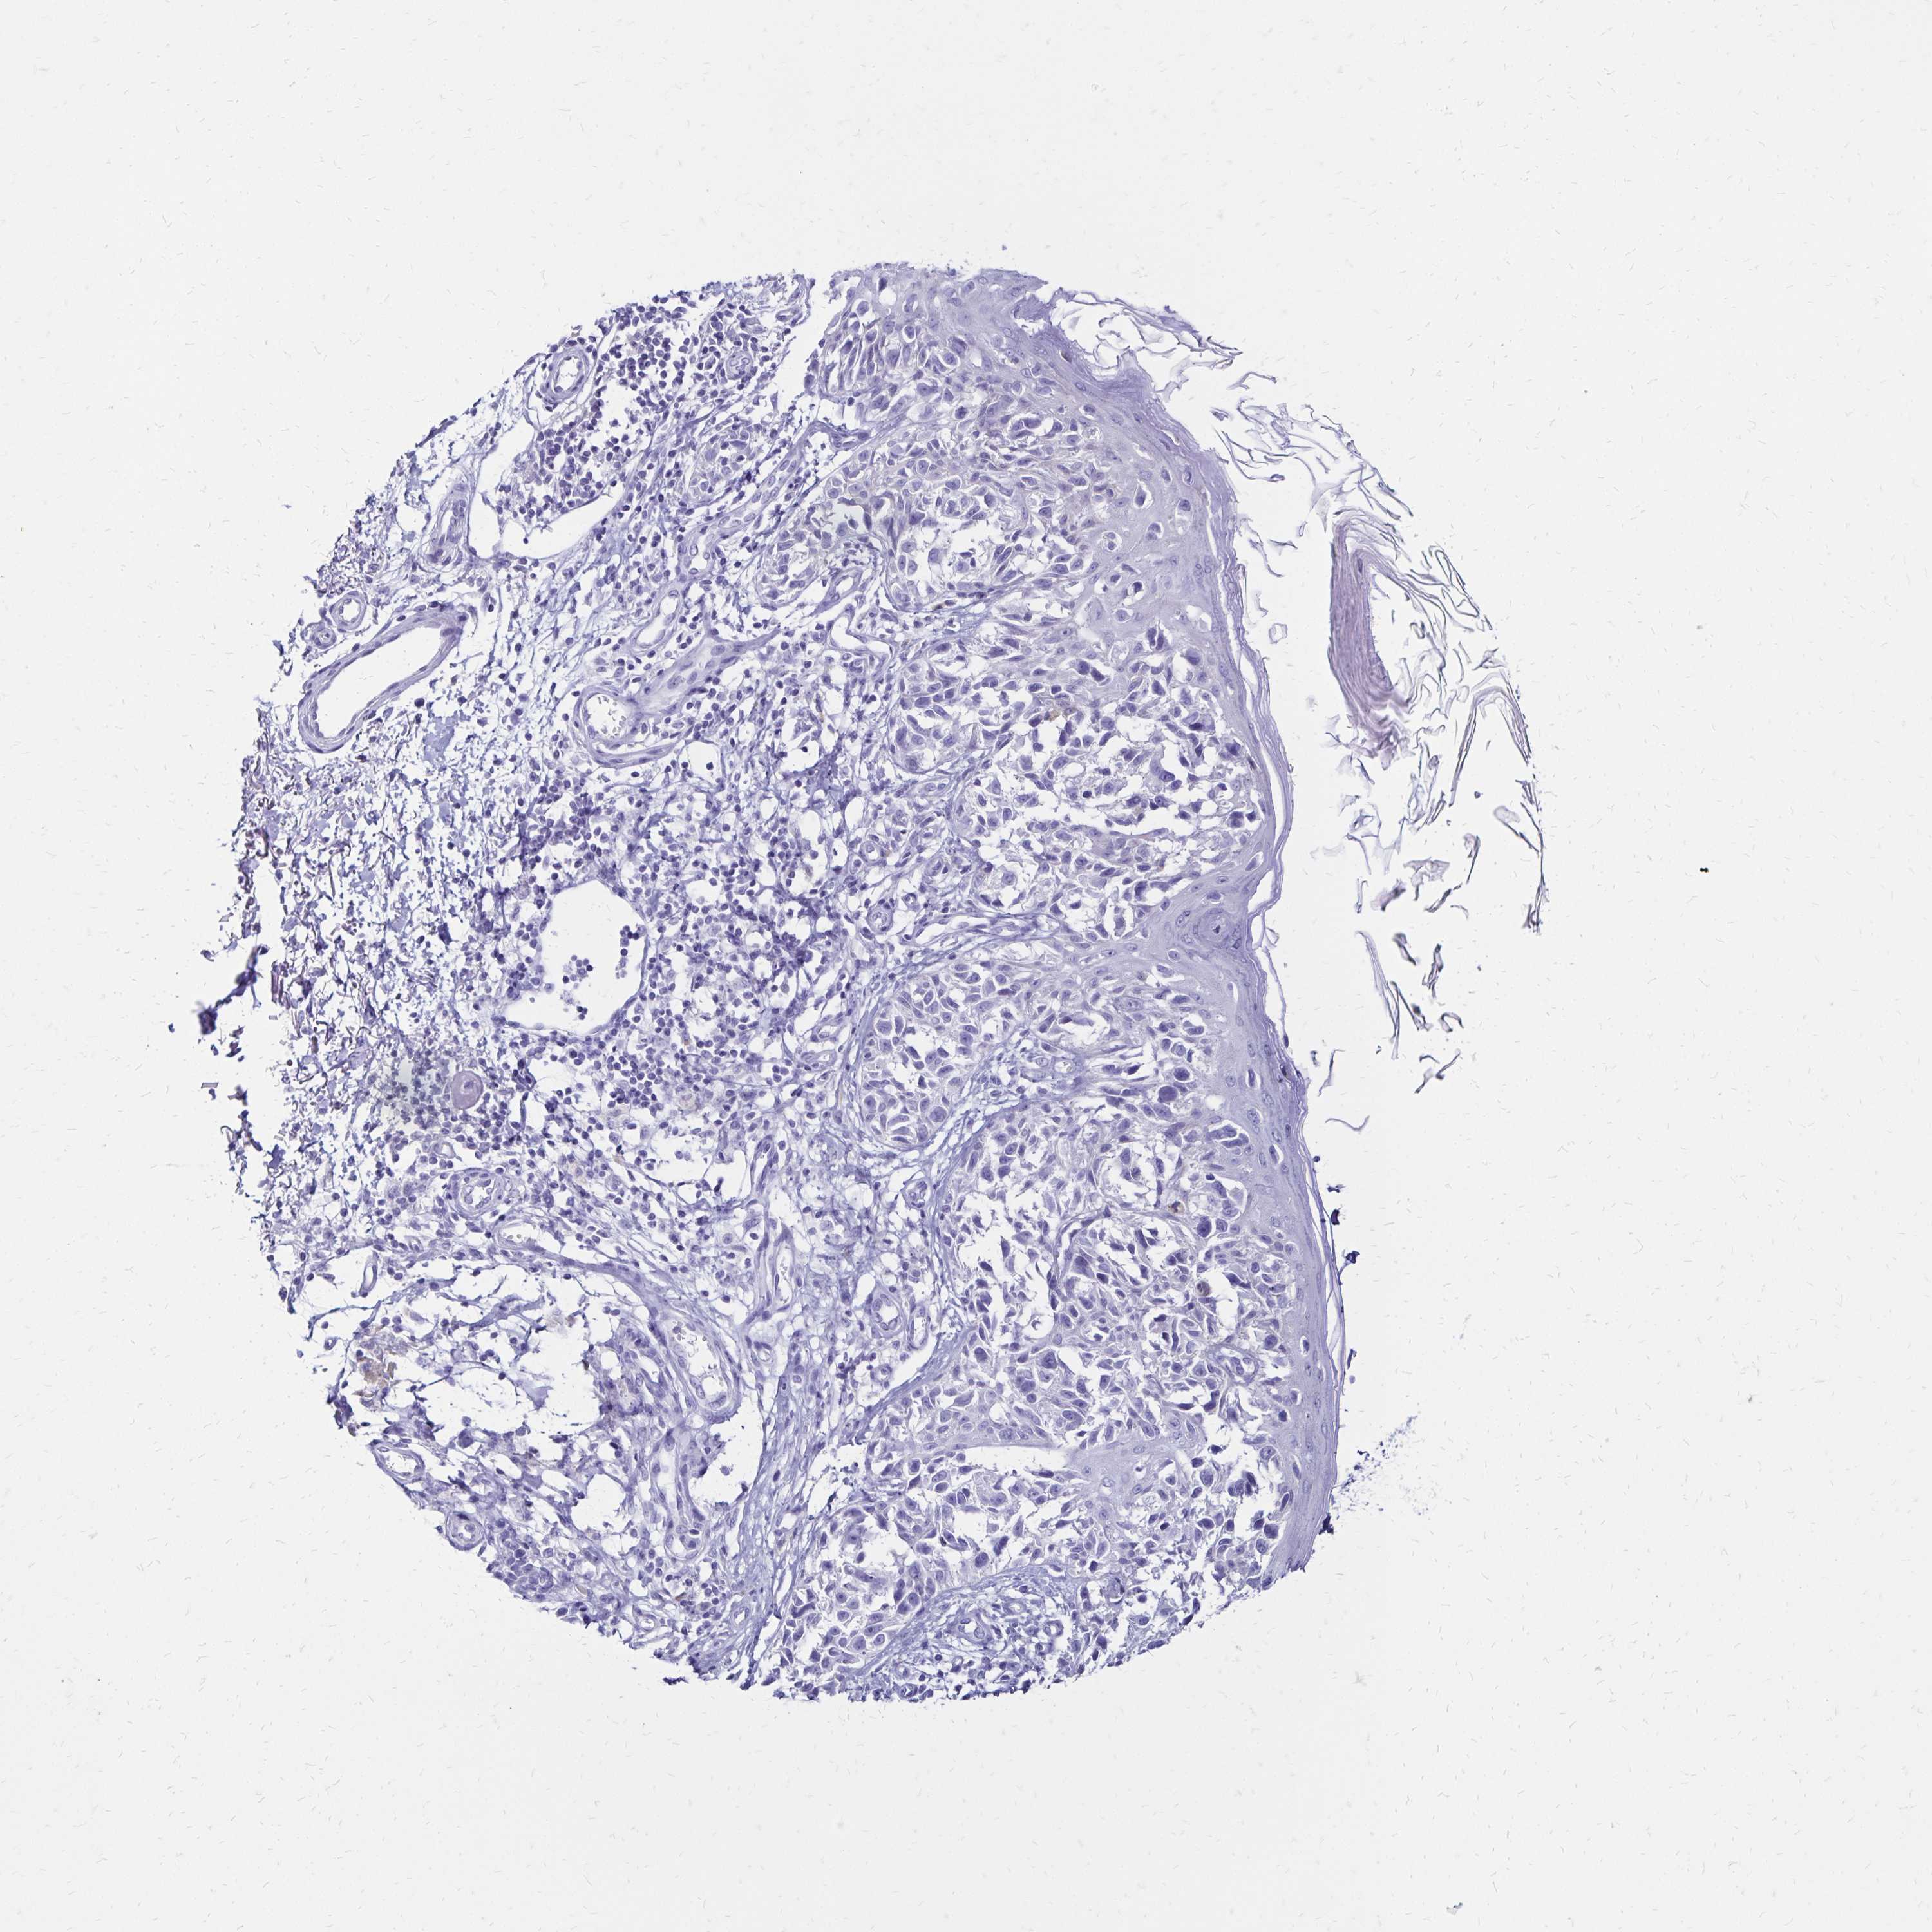

MELANOMA - Protein expressioni

A mouse-over function shows sample information and annotation data. Click on an image to view it in a full screen mode. Samples can be filtered based on level of antibody staining by selecting one or several of the following categories: high, medium, low and not detected. The assay and annotation is described here.

Note that samples used for immunohistochemistry by the Human Protein Atlas do not correspond to samples in the TCGA dataset.

Antibody stainingi

Antibody staining in the annotated cell types in the current human tissue is reported as not detected, low, medium, or high, based on conventional immunohistochemistry profiling in selected tissues. This score is based on the combination of the staining intensity and fraction of stained cells.

Each image is clickable and will lead to virtual microscopy that enables deeper exploration of all samples and also displays staining intensity scores, fraction scores and subcellular localization as well as patient and tissue information for each sample.

Antibody HPA035363

Antibody HPA035364

Malignant melanoma, NOS

Malignant melanoma, Metastatic site